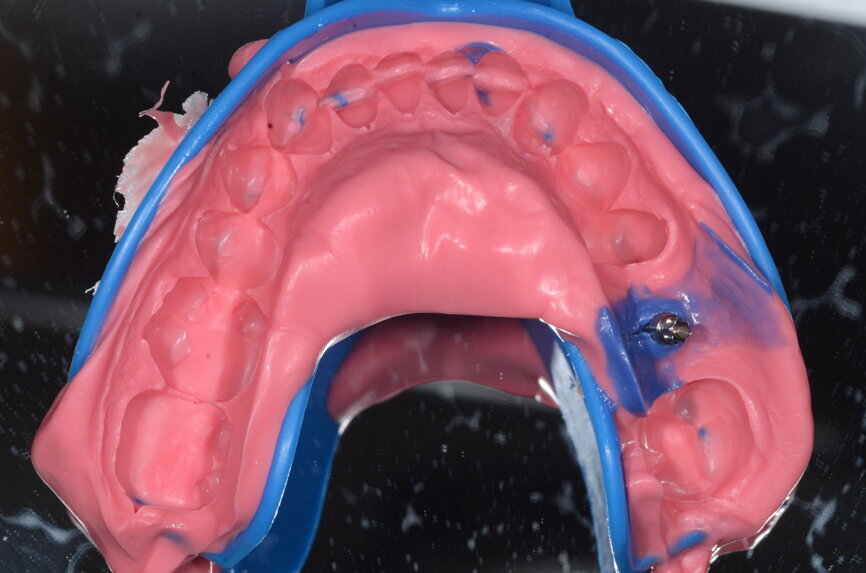

Fig. 10: Impression tray with impression post retained.

The patient, a 67-year-old non-smoking man without any relevant medical history, was referred to the office with a missing tooth (#36) due to persistent apical periodontitis. The tooth had been extracted more than one year prior to the procedure and the molar site was well maintained and fully healed (Fig. 1). A CBCT scan showed that the patient had favourable bone availability (Fig. 2), on which basis a one-stage placement of a 5.5 × 10.0 mm Straumann BLX implant was planned. After surgically installing the implant (Figs. 3–7), Salvesen allowed the surrounding soft tissue to mature and heal for six weeks (Fig. 8). He then removed the healing abutment to begin the prosthetic procedures for a temporary crown (Figs. 9 & 10). A stone master cast was made in the laboratory, and a temporary screw-retained PMMA crown was manufactured over a Straumann wide base temporary abutment for the crown (Fig. 11) and placed on to the implant (Figs. 12–14).

After 12 weeks, Salvesen removed the temporary crown, revealing that the soft tissue had healed very well (Fig. 15). He then began the digital workflow. For the final crown, a digital impression was taken with a 3Shape intra-oral scanner, using a Straumann CARES scan body. A monolithic zirconia crown was then seated passively on to the implant in a healed and preconditioned soft-tissue environment (Figs. 16–19).